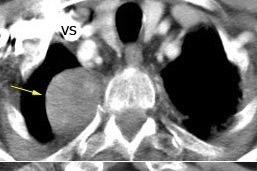

Aneurisma de arteria bronquial

Compresión por art. pulmonares.

Hipertensión pulmonar

Ausencia de válvula pulmonar

Anillos vasculares

Broncomalacia Post-Tb

Masas mediastínicas. (Bocio, etc.)

Aneurisma aórtico

Duke RA et al. Compression of Left Main Bronchus and Left Pulmonary Artery by Thoracic Aortic Aneurysm . AJR 1987

Wilson SR et al. CT Visualization of Mediastinal Bronchial Artery Aneurysm. AJR 2006

Zhong M-Y et al. Multi-slice computed tomography assessment of bronchial compression with absent pulmonary valve. Pedriat Radiol 2014